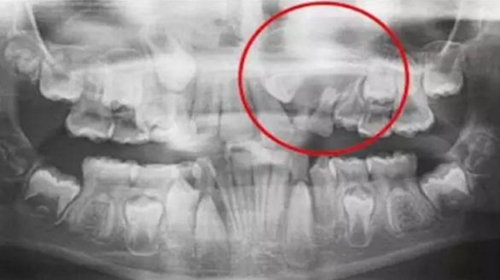

一名 23 區(qū)的9歲患者,在診所接受檢查時(shí)發(fā)現(xiàn)口內(nèi)中存在大范圍含牙囊腫[圖1]。由于上頜竇下沿出現(xiàn)大范圍突出,迫切需要接受囊腫去除手術(shù)[圖2和3]。

囊腫去除[圖2]